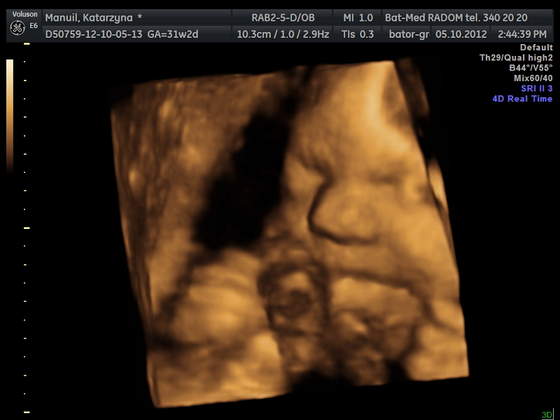

Byłam z Mamą i Mężem i wszyscy troje mieliśmy łezki w oczach jak zobaczyliśmy Młodą na 4D:)

pozdrawiamy :) z uśmiechem Jasi: ---> uśmiech Jasi

Mąż twierdzi, , że Jasia na ostatniej fotce, złości się identycznie jak ja ;)

• manuil katarzyna_10.jpg

manuil katarzyna_10.jpg

20,2 KB · Wyświetleń: 91